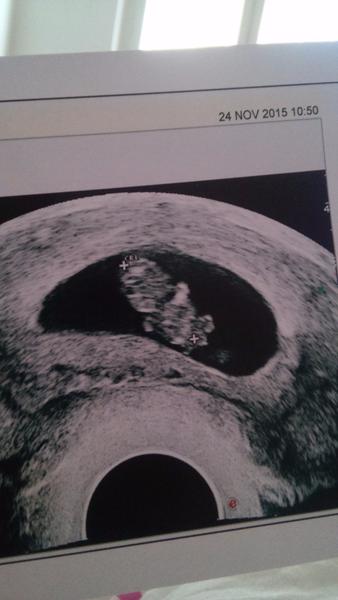

@smoulinka1505 ahoj...krasna foto. Podla kalendara som 9+3 ale podla doktora menejbo tyzden a poradnu mam nedohladne tak cakam 🙂

@depi ja podla kalendara zajtra zacinam 10t.doktor zatial nehovori nic.iba mi vzdy povie ze ani nedycham ked pozeram na ten moitor.aj ti byva zle?

@fergiea jejoooo, krasna fotecka. Uz nech sa aj nam zadari. Mala by som mat teraz ovulku, meriam si BT, ale v tom grafe sa moc nevyznam a ani neviem ci to znaci ovulku. Ale ovu test som mala pred dvoma dnami pozitivny. Tak drz palceky a pekne nas ostatne nakaz 🙂 inak ako sa citis? už viac papas? lebo brusko ti krasne rastie 😉

@smoulinka1505 nevracam ale zle mi byva...a to zo vsetkeho...z hladu, potom ked sa najem, a kyselina kazdy vecer....ale posledne dni ma trapia uz len vecer kyselina...a ked idem von s malou radsej s muzom byva mi dost slabo